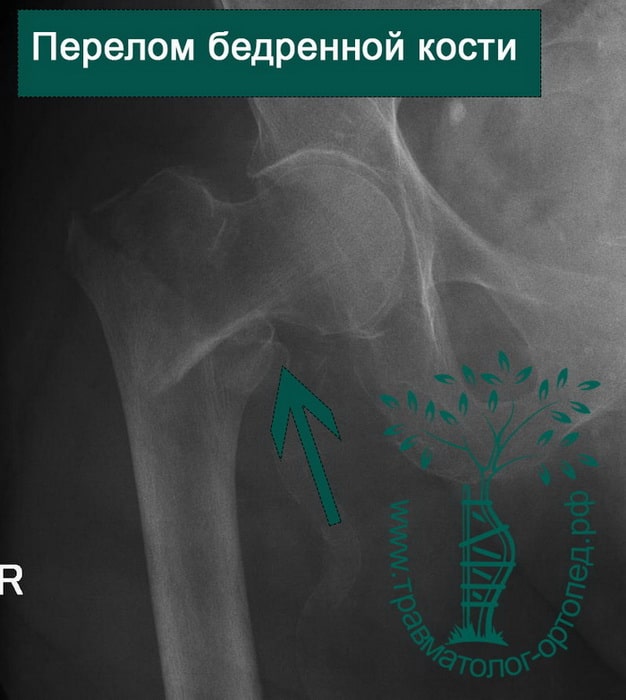

Классификация переломов диафиза бедренной кости: Иллюстрации и информация